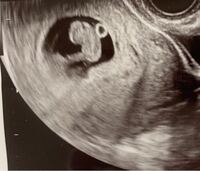

Cabeza_kumamoto 4 likes Interest 妊娠・出産 (ラムジーメソッドについて) (頭の幅) 453ミリ ac(腹部周囲長) 1292ミリ fl(大腿骨長) 251ミリ 体重は225グラム、頭からお尻まで13センチで足を伸ばせばセンチ弱とのこと。 順調だそうです 『ぜひとも性別をお願いします!』で、エコー開始数秒#ラムジーに関するブログ新着記事です。はなちゃん・ラムちゃんの通院日シリーズ最壊 "ワイルド スピード ジェットブレイク"ラムジーの通院 ② 診察と結果ラムジーの通院 ①これが、僕たちの大き

妊娠13週で昨日検診でした エコー写真をもらったのですが これって男の子っ Yahoo 知恵袋

10週エコー写真 見方を教えてください 10w4dでcrl3 5cmのエコー写 避妊 教えて Goo

エコー写真の見方を教えてください エコー写真の見方を教えてください 妊娠 教えて Goo